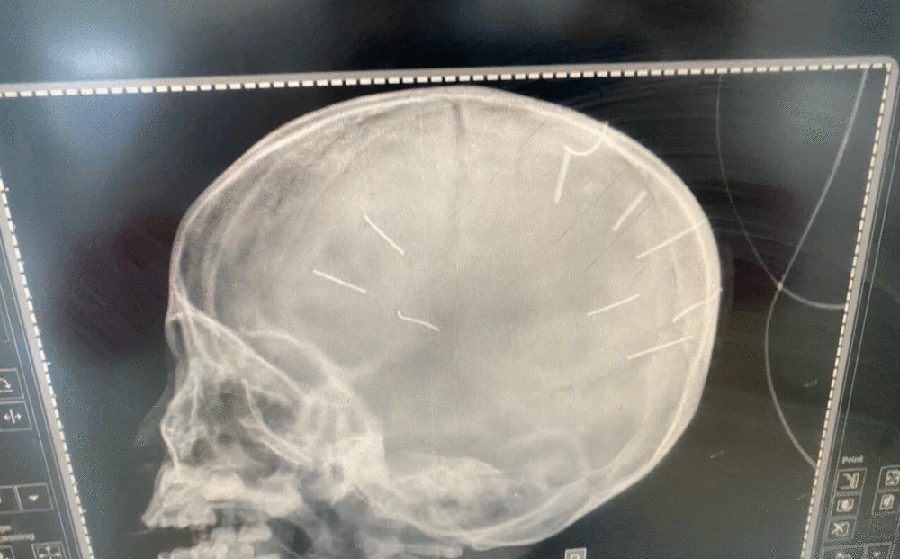

Trước đó, đại diện Phòng Công tác xã hội, Bệnh viện đa khoa Xanh Pôn (Hà Nội) thông tin, đơn vị đang phối hợp với cơ quan công an để làm rõ nguyên nhân bé gái 3 tuổi nhập viện trong tình trạng có nhiều vật giống đinh ghim vào hộp sọ, nghi do bị bạo hành.

Ngày 17-1, cháu bé được mẹ đưa tới Bệnh viện Đa khoa huyện Thạch Thất, sau đó được chuyển lên Bệnh viện Đa khoa Xanh Pôn. Khi được đưa vào bệnh viện, cháu gái trong tình trạng hôn mê sâu. Bệnh nhân sau đó được bác sĩ chẩn hộp sọ có hình ảnh cản quang, hôn mê nghi viêm màng não.